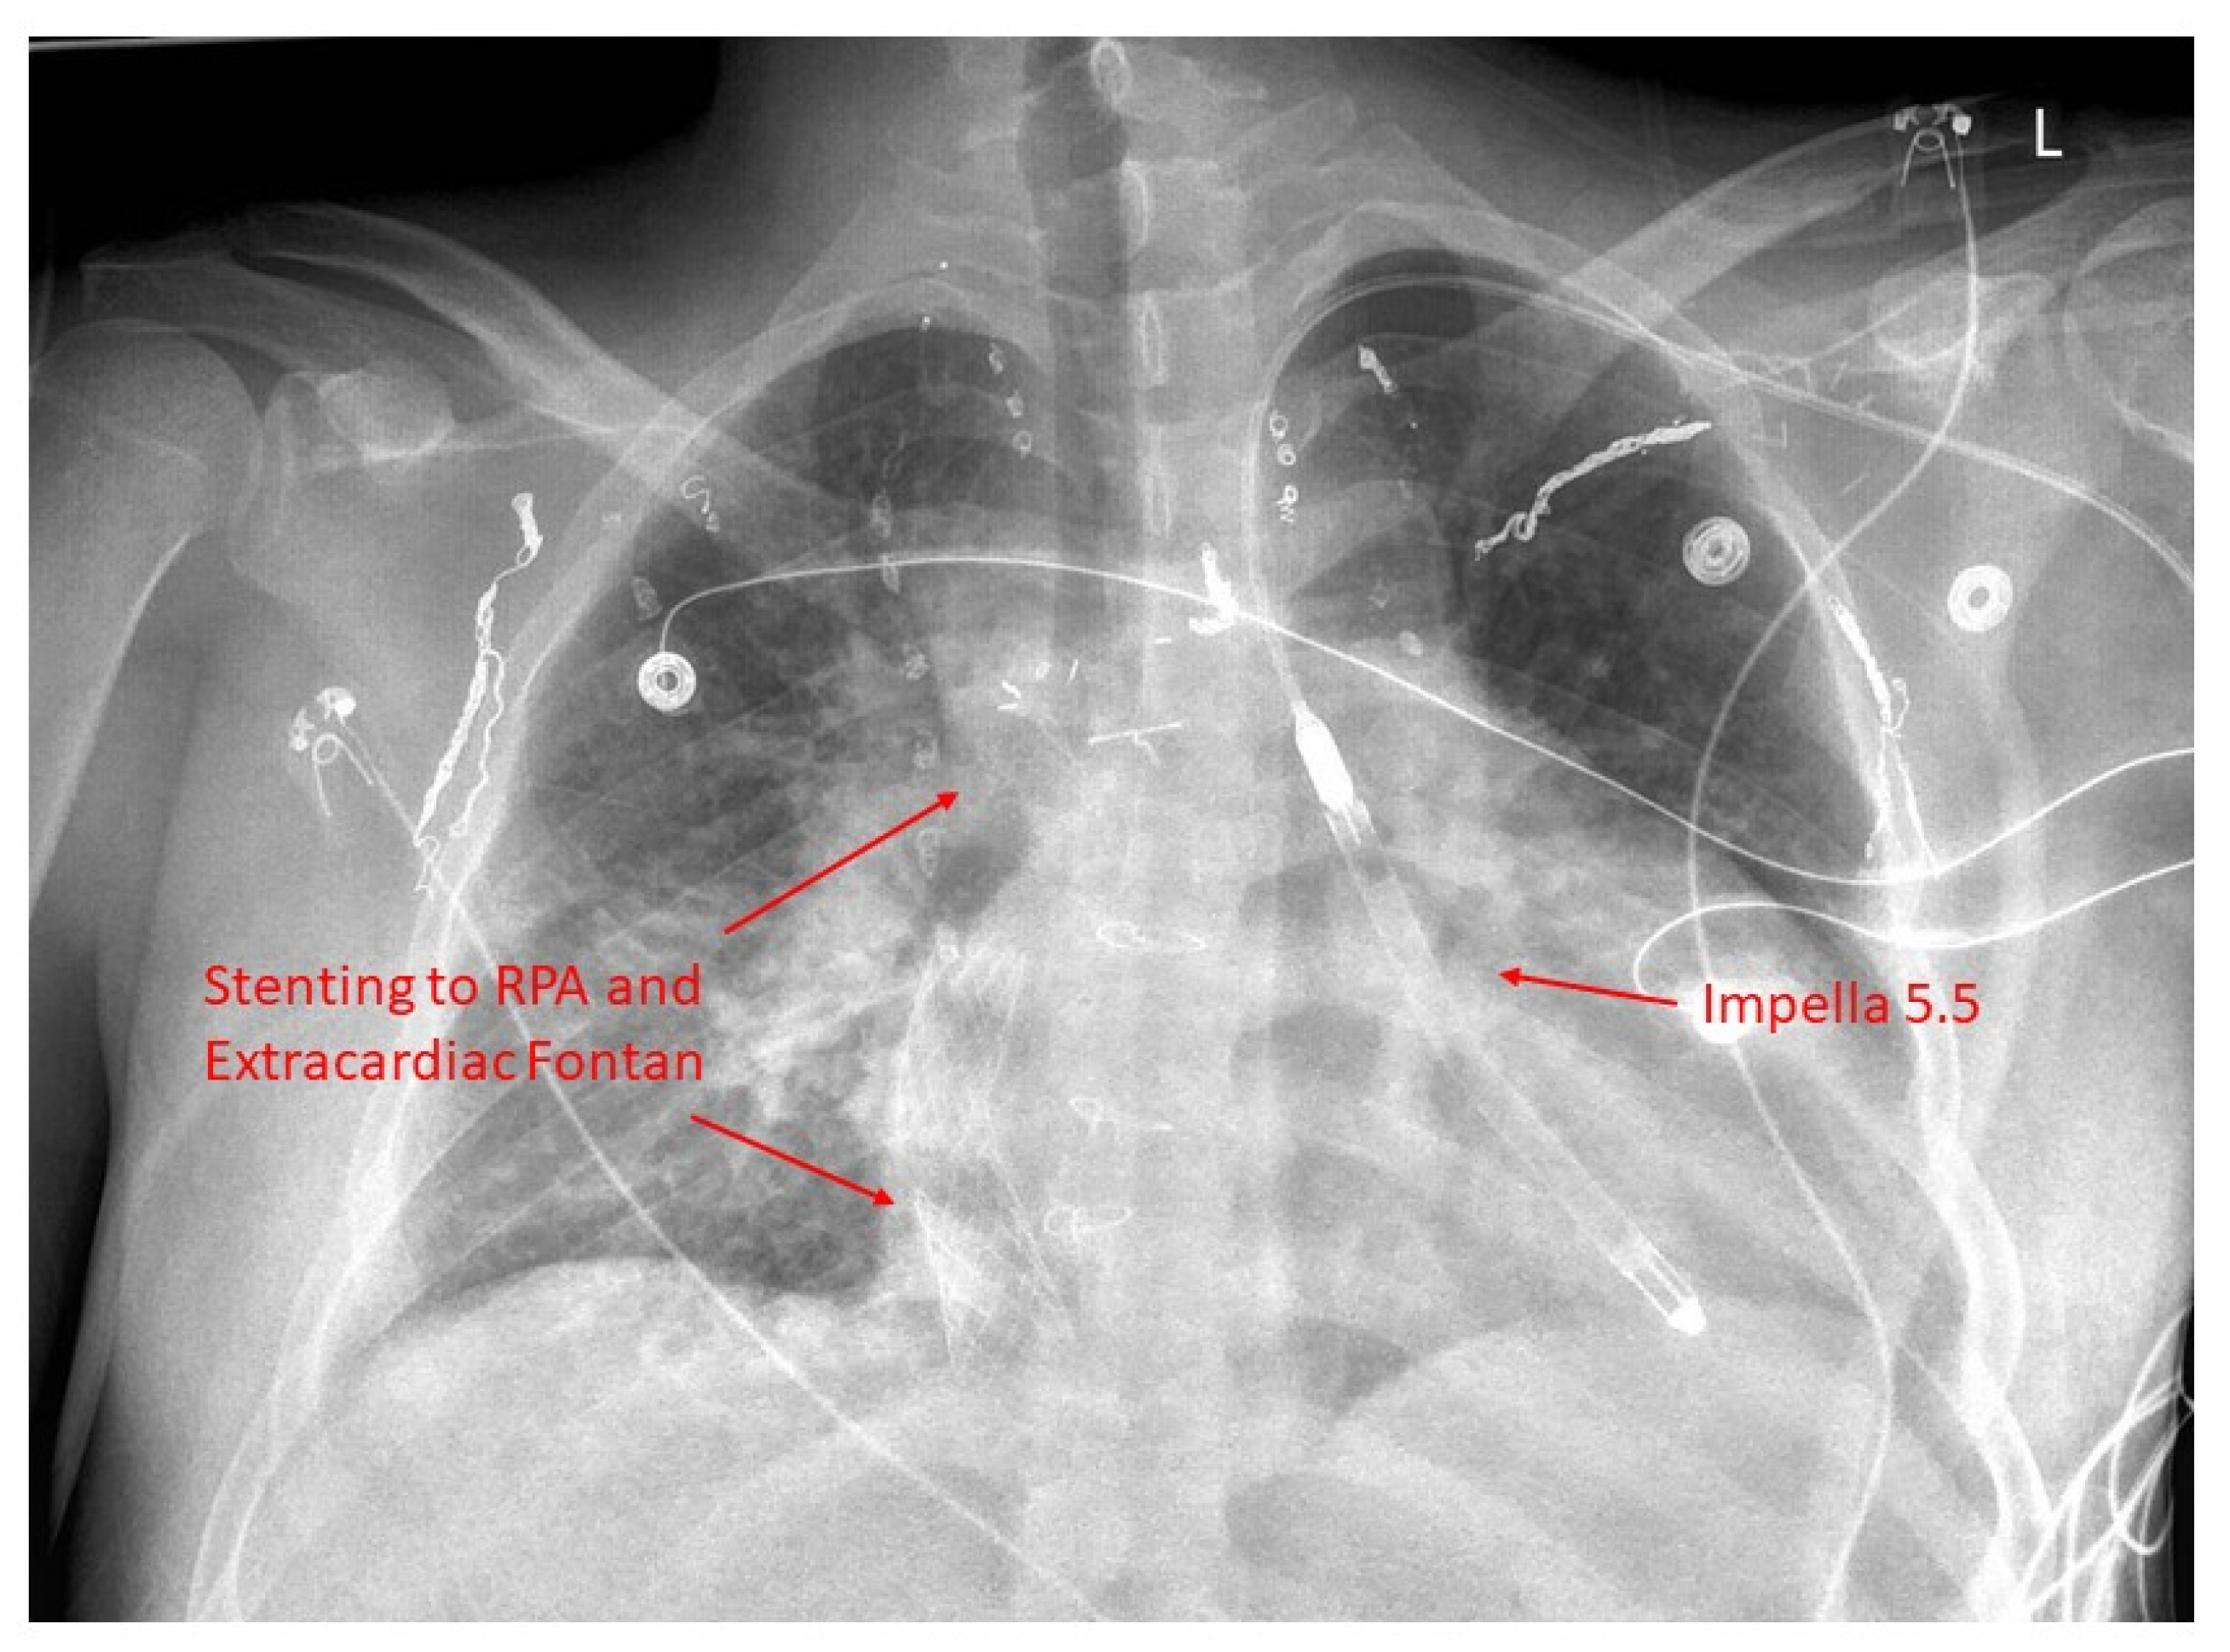

22. Fontan Pathway Obstruction

- Mets, J.M.; Bergersen, L.; Mayer, J.E.; Marshall, A.C.; McElhinney, D.B. Outcomes of stent implantation for obstruction of intracardiac lateral tunnel Fontan pathways. Circ. Cardiovasc. Interv. 2013, 6, 92–100. [Google Scholar] [CrossRef]

- Agasthi, P.; Jain, C.C.; Egbe, A.C.; Hagler, D.J.; Cabalka, A.K.; Taggart, N.W.; Anderson, J.H.; Cetta, F.; Connolly, H.M.; Burchill, L.J.; et al. Clinical Outcomes of Percutaneous Fontan Stenting in Adults. Can. J. Cardiol. 2023, 39, 1358–1365. [Google Scholar] [CrossRef]